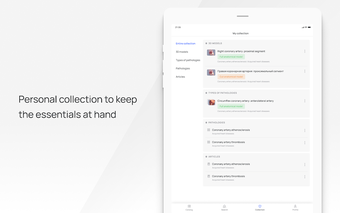

In this atlas of human pathologies you can learn about diseases, their causes, symptoms, and treatment. It contains all the essential information about the anatomy of the human body and its organs. You will be able to study diseases and their causes from an anatomy point of view. It contains information about diseases, their symptoms, and their treatment. In addition, you will be able to view 3D models of all the important organs of the human body.

All 3D pathology models are developed in close cooperation with medical experts of hospitals and research centers. They are thought out to the very smallest detail. Each category contains models of healthy organs.

VOKA Pathology 3D is an educational tool for medical students, lecturers, and physicians. It can help you learn about human anatomy and pathology.